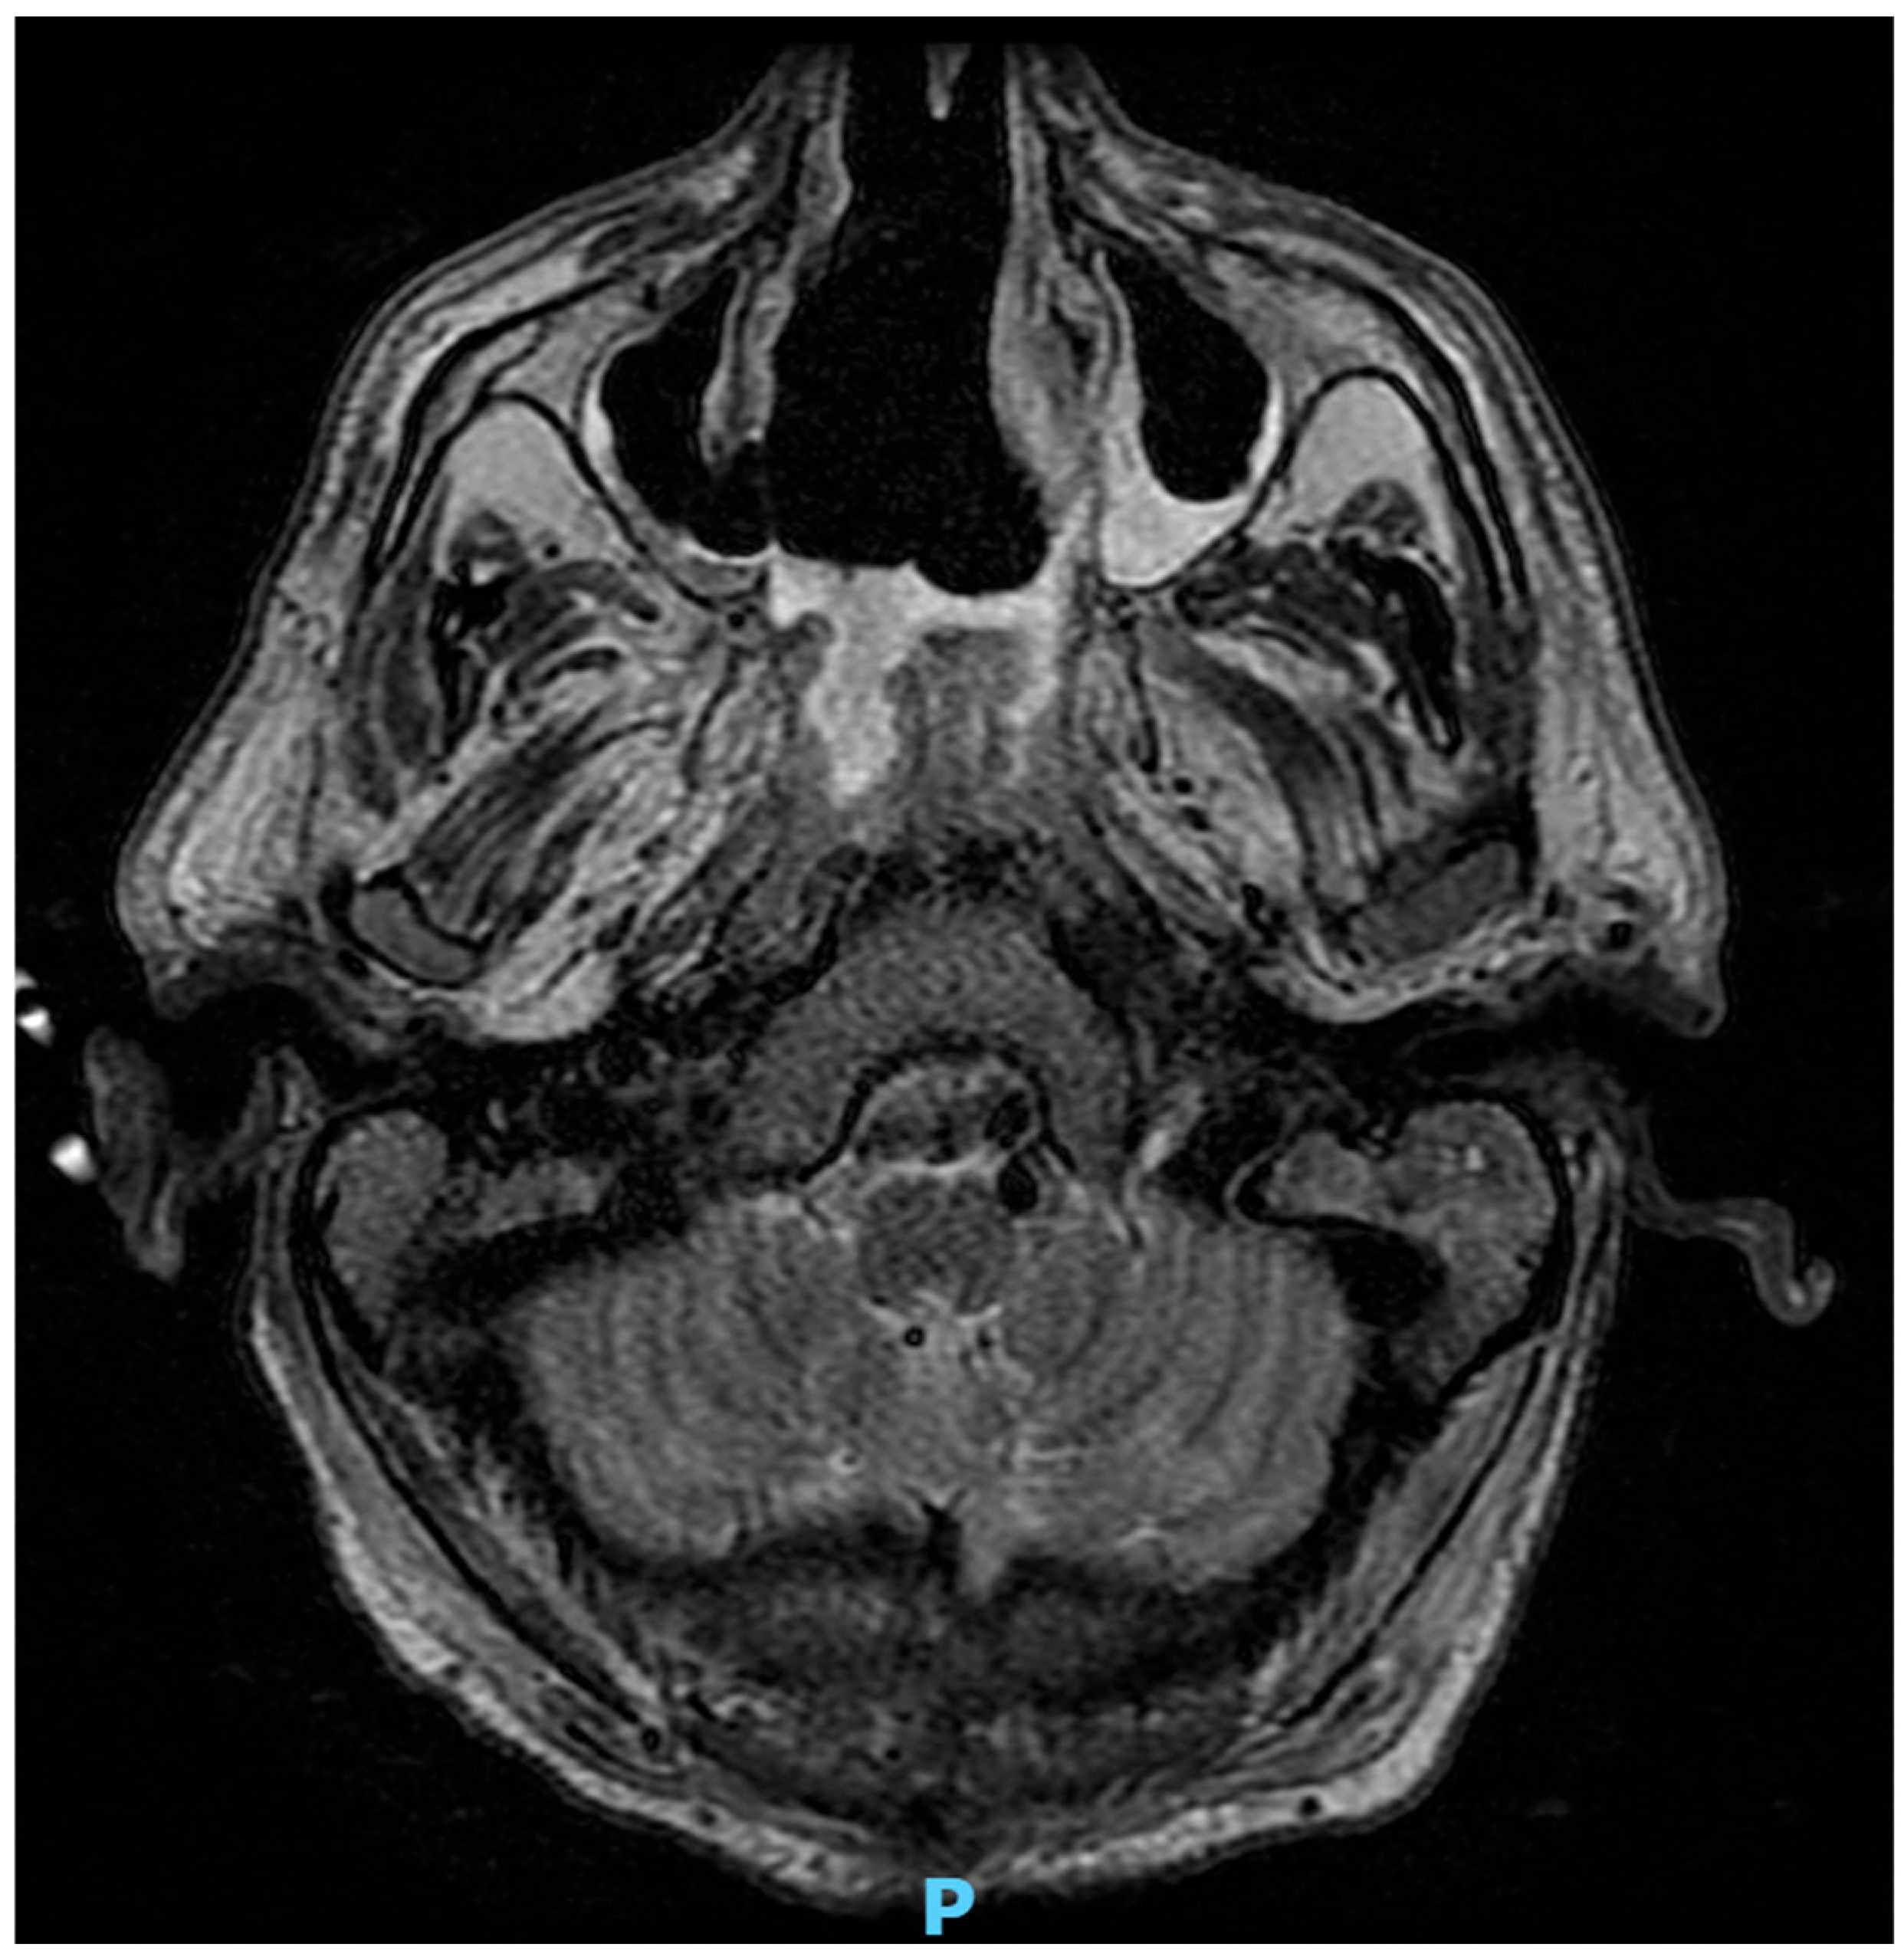

5.2. Rhino-Orbital-Cerebral Mucormycosis

- Herrera, D.; Dublin, A.; Ormsby, E.; Aminpour, S.; Howell, L. Imaging Findings of Rhinocerebral mucormycosis. Skull Base 2009, 19, 117–125. [Google Scholar] [CrossRef] [PubMed]

- Gamaletsou, M.N.; Sipsas, N.V.; Roilides, E.; Walsh, T.J. Rhino-Orbital-Cerebral Mucormycosis. Curr. Infect. Dis. Rep. 2012, 14, 423–434. [Google Scholar] [CrossRef]